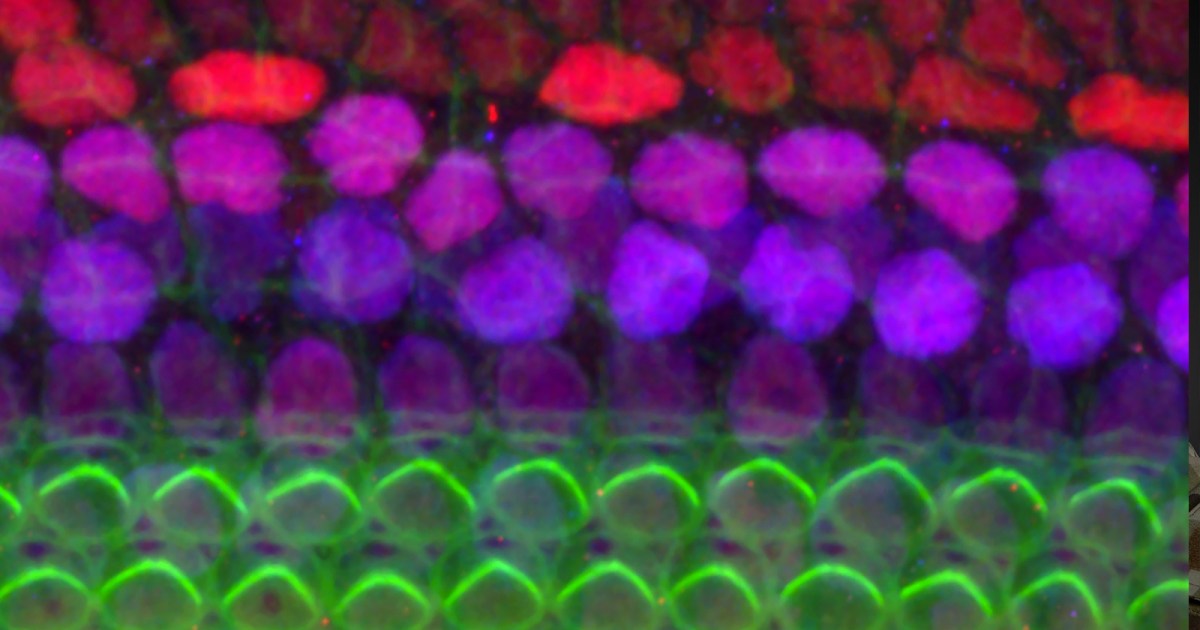

wyzwanie: Komórki rzęsate to maleńkie receptory w uchu, które przekształcają wibracje w sygnały elektryczne, które nasz mózg może zinterpretować jako dźwięk. Rodzimy się z około 16 000 w każdym ślimaku, ale z biegiem czasu niektóre z nich ulegają uszkodzeniu lub umierają z powodu chorób, starzenia się i narażenia na głośne dźwięki.

Jest to częsta przyczyna utraty słuchu i chociaż obecnie nie ma sposobu na odwrócenie uszkodzeń komórek rzęsatych u ludzi, naukowcy byli w stanie stymulować regenerację i przywracać słuch u myszy poprzez Wstrzykiwanie terapii genowych w ślimaku.

sposób w: Naukowcy z University of Rochester przyjrzeli się niedawno przewodowi ślimakowemu, małemu kanałowi między ślimakiem a mózgiem, zarówno u ludzi, jak iu myszy.

dla nich Stańktóry jest teraz opublikowany w Science Translational Medicine, wykorzystali technologię obrazowania i modelowania do mapowania przepływu płynu mózgowo-rdzeniowego z różnych części mózgu przez kanał do ślimaka.

Na tej podstawie postawili hipotezę, że terapia genowa mająca na celu przywrócenie słuchu u głuchych myszy trafiłaby do ślimaka myszy, gdyby wstrzyknięto ją do zbiornika płynu mózgowo-rdzeniowego u podstawy czaszki zwierzęcia.

I mieli rację. Adenowirus przenoszący terapię genową dotarł do ucha wewnętrznego, zwiększając produkcję białka przywracającego słuch głuchym myszom. pojemność Ta terapia genowa Przywracanie słuchu było znane przed tym badaniem, ale to pokazuje, że istnieje bezpieczniejszy, mniej inwazyjny sposób na wprowadzenie go do ślimaka.

dolna linia: Chociaż nadal nie wiemy, czy to zadziała u ludzi, znalezienie lepszej ścieżki zarządzania może pomóc zapewnić naukowcom, że przypadkowo nie spowodują więcej szkód, jeśli którakolwiek z terapii przejdzie do badań klinicznych.

„Te odkrycia pokazują, że transfer płynu mózgowo-rdzeniowego obejmuje dostępną ścieżkę dostarczania genów do ucha wewnętrznego osoby dorosłej i może stanowić ważny krok w kierunku zastosowania terapii genowej w celu przywrócenia słuchu u ludzi” Powiedział Starszy autor Maiken Nedergaard.